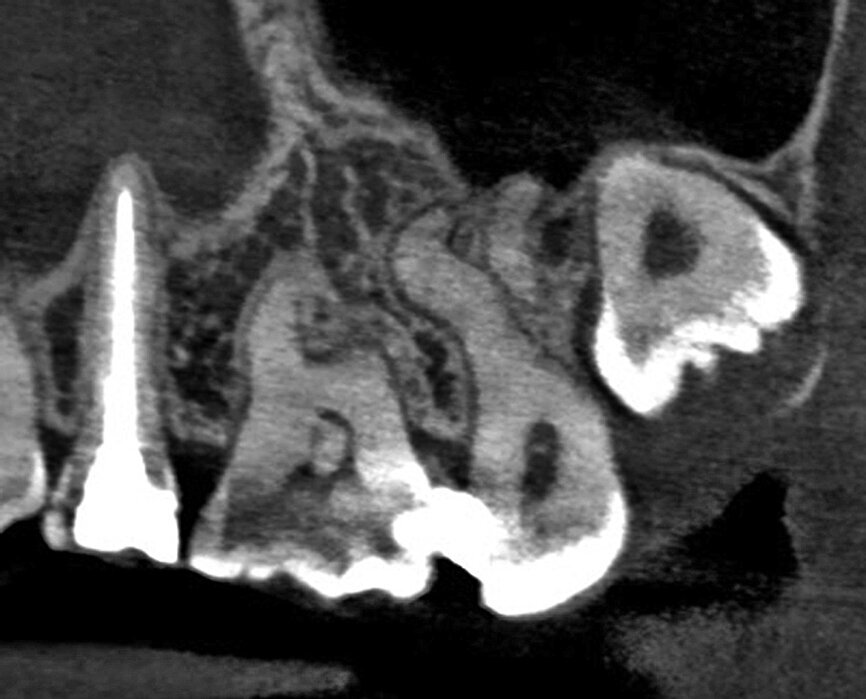

The patient, a 25-year-old female, reported with irreversible pulpitis on her maxillary second left molar. The tooth was temporarily restored with Intermediate Restorative Material (IRM, Dentsply Sirona) and the patient complained about continuous food impaction between her maxillary left, first and second molar teeth (Fig. 2). A periapical radiograph revealed that the temporary restoration was not sealing at the gingival margin (Fig. 3). Also, visible on the periapical radiograph was evidence of possible curvatures in the mesiobuccal and distobuccal roots. It was decided, with the consent of the patient, to take a limited field of view CBCT scan to explore the anatomy of this tooth. The CBCT scan revealed the presence of three root canal systems when viewed in the axial plane; and in the sagittal plane, evidence of severe root curvatures were present in the mesiobuccal and distobuccal root canal systems. It was decided to do a more in-depth investigation as a result of this complex anatomy, using the 3D Endo Software (Dentsply Sirona).

In the first step, ‘Diagnosis and Pathology’, the imported scan was reviewed in the axial, sagittal and coronal planes. The software has the ability to present a 3-D reconstructed view where the transparency of the teeth can be changed (Figs. 4a–d).

The second step, ‘3D Tooth Anatomy’, involved selecting the tooth to be examined and the entire volume was cropped to only leave the data of interest behind (Fig. 5). In the third step, ‘Canal System’, the number of root canals were identified and each root canal was then mapped separately by identifying the orifice and radiographic apical foramen of each root canal (Fig. 6).

With the fourth step, ‘3D Canal Anatomy’, the software made a proposal of the canal anatomy (Fig. 7), but the operator can make corrections according to the canal configuration that can be viewed in different planes in the software. Figures 8 to 10 show the mapping of the palatal, mesiobuccal, and distobuccal root canal systems.

During the fifth step, ‘Treatment Plan’, the software projected ISO size 06 instruments into the canals (Fig. 11), which allowed the operator to visualise the internal anatomy of the canals, check straight line access, and modify the proposed access if necessary. A rubber stop on the files can then be digitally adjusted to a coronal reference point of choice that will then indicate the proposed working length for each root canal system. This view can also be rotated in 3-D to alert the operator of the angle and direction of curvatures in the root canal systems (Fig. 12). The step after ‘treatment plan’ is to select a master file from a preloaded database of endodontic file systems that will most likely result in optimal canal preparation for that specific shape or diameter of a canal. Considering the s-shaped curvatures in all three root canal systems as well as the sharp curvatures in different planes, it was decided to use the Primary WaveOne Gold file (25/07) in the palatal canal and the Small WaveOne Gold file (20/07) for root canal preparation in the two-challenging buccal root canal systems (Fig. 13). The selected instruments were then displayed in the root canal systems and the operator again digitally rotated and visualised the root canal anatomy in 3-D (Fig. 14).